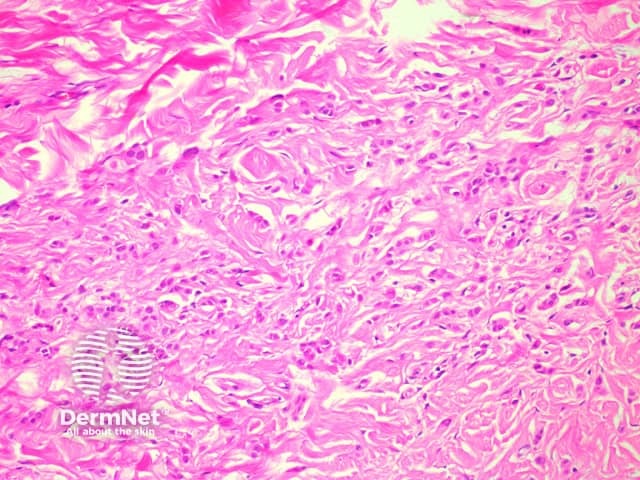

Microscopic examination of angiomyofibroblastoma demonstrates a well-circumscribed tumour without a capsule and with variable cellularity. Hypocellular areas are collagenous (figure 1) or myxoid with some small-medium sized vessels. Hypercellular areas, located predominately around the vessels, contain characteristic plump round/oval shaped cells with relatively uniform nuclei without remarkable atypia (figure 2). Occasional multinucleated and binucleated cells may be seen.

Figure 2